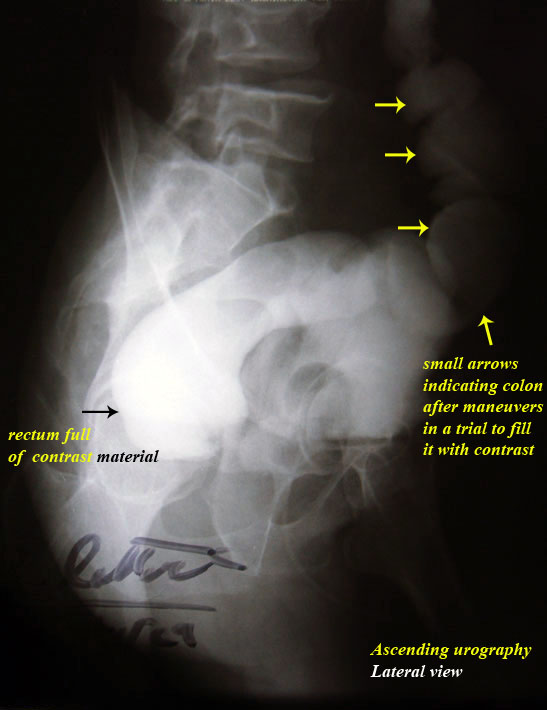

treatment. By difficulty we persuaded him to do ascending urography

" see photos".

Do you think that these photos were

convincing for the patient?

In order to satisfy him by this

diagnosis we advised him to defecate after the ascending urography,

as he saw by his own eyes the dye passing instead of stool, he

accepted !!